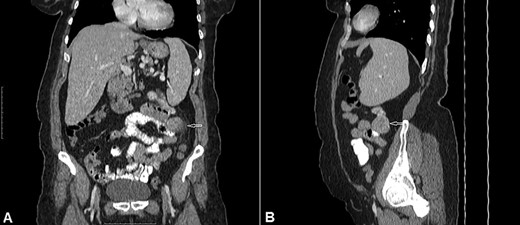

A 54-year-old woman presented with a history of multiple episodes of melaena and haematochezia accompanied by colicky abdominal pain and fatigue for the previous 3 days. Other than hypertension she did not have any other comorbidity. On primary physical examination she was pale and had a slight tachycardia but was normotensive. Abdominal examination was unremarkable. Digital rectal examination confirmed melaena stool mixed with fresh blood. Laboratory tests revealed a low haemoglobin of 7.2 g/dl. Clotting tests were normal. The patient was commenced on IV fluids and a transfusion with packed red blood cells. Emergency gastroscopy to the third part of the duodenum did not show any evidence of active bleeding. She continued to pass large amounts of melaena and fresh blood and her haemoglobin was noted to have dropped to 5.4 g/dl. A colonoscopy was decided against. She received further packed red blood cells and underwent an urgent computed tomography (CT) scan with oral and IV contrast. This showed a well-defined homogenous extraluminal mass (4 × 3.5 cm) in the proximal jejunum with mesenteric neovascularisation. There was no evidence of intra-abdominal metastases or enlarged lymph nodes (Figs 1 and 2). These findings were most suggestive of a bleeding GIST. Angiography and embolisation facilities were not available in our institution. The patient was becoming unstable and so an urgent laparotomy was required.

CT of the abdomen with Intravenous and oral contrast (A) coronal section, (B) sagittal section shows: well-defined extraluminal mass of proximal jejunum (white arrow).